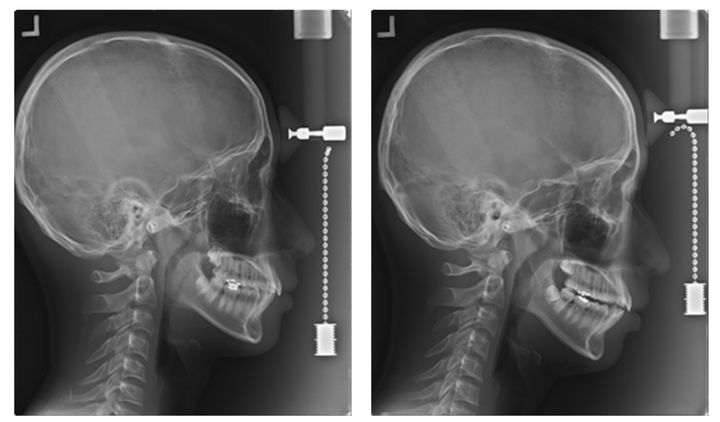

[서울=뉴시스] 1일 대한치과의사협회에 따르면 최근 안전 및 효과가 검증되지 않은 '셀프 치아장치' 사용으로 인해 오히려 구강 건강을 해치는 사례가 발생하고 있어 소비자의 각별한 주의가 요구되고 있다. 사진은 '셀프 치아장치' 로 인한 '턱관절 장애' 및 '부정교합' 유발 사례로 셀프 치아장치 장착 전(왼쪽)과 장착 후 모습이다. (사진=대한치과의사협회 제공) 2025.09.01. [email protected] *재판매 및 DB 금지